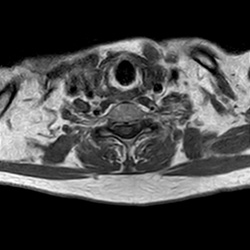

MRI_eeAX_T2W_Lumbal_1002

25 photos